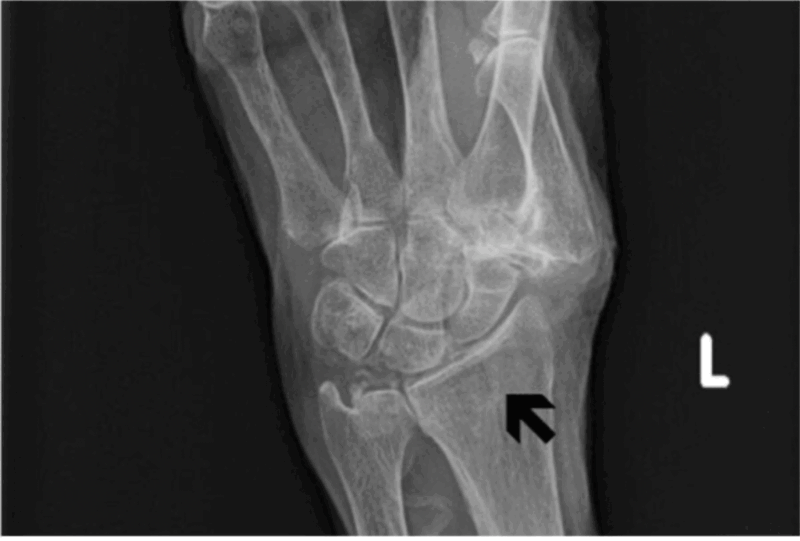

診察したところ, 手首の変形はありませんでしたが, 腫れていて, 腕の骨(橈骨とうこつ)の手首に近い部分を圧すと痛がるので, 橈骨遠位端骨折と診断して, X線写真を撮るようにオーダーを入れました.

橈骨遠位端に縦に黒い線として写るヒビ(骨折線)が入っていますが, ズレはありません.

撮像されたX線写真を見たところ, 橈骨遠位部に縦にヒビが入った橈骨遠位端の亀裂骨折でした. ギプス製の板(ギプスシーネ)をあてがって, 包帯を巻いて固定しようとしたところ, 付き添いの家人から, 認知症のため全部外してしまうので, ギプスを巻いてもらいたいと言われました. 腫れが少なかったので, 今後も腫れる心配は少ないと判断して, プラスチック製のギプスを巻きました. 3週間後にギプスを外すので, 予約を入れました.